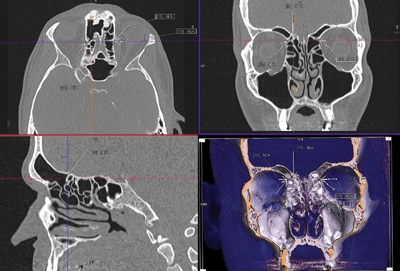

Both Dr Kennedy and Dr Stammberger influenced my selection of the CT images needed to meet the surgical requirements. Most memorable for me was the time spent at one of the earlier AAO meetings in San Antonio, where Dr Stammberger and I spent countless hours establishing the course of the basal lamella of the middle turbinate, a concept well-displayed in his drawings of the structure. This concept, as well as others, is demonstrated with standard orthogonal, multiplanar reconstructions and with the 3D surface rendered images ‘scattered’ throughout his famous text book. Dr Stammberger used his excellent educational skills to optimal advantage when he illustrated his message with concrete and detailed imaging, thereby informing the reader of the essence of sinus surgery, and the information needed for its optimal performance [2-4].

Evolution of sinus imaging: (Figure A) X-ray polytomography; (Figure B) Coronal CT scan; (Figure C) CT MPR and surface-rendered 3D image; (Figure D) 3D CT Stereoscopic Image showing the anatomy in the sagittal plane.